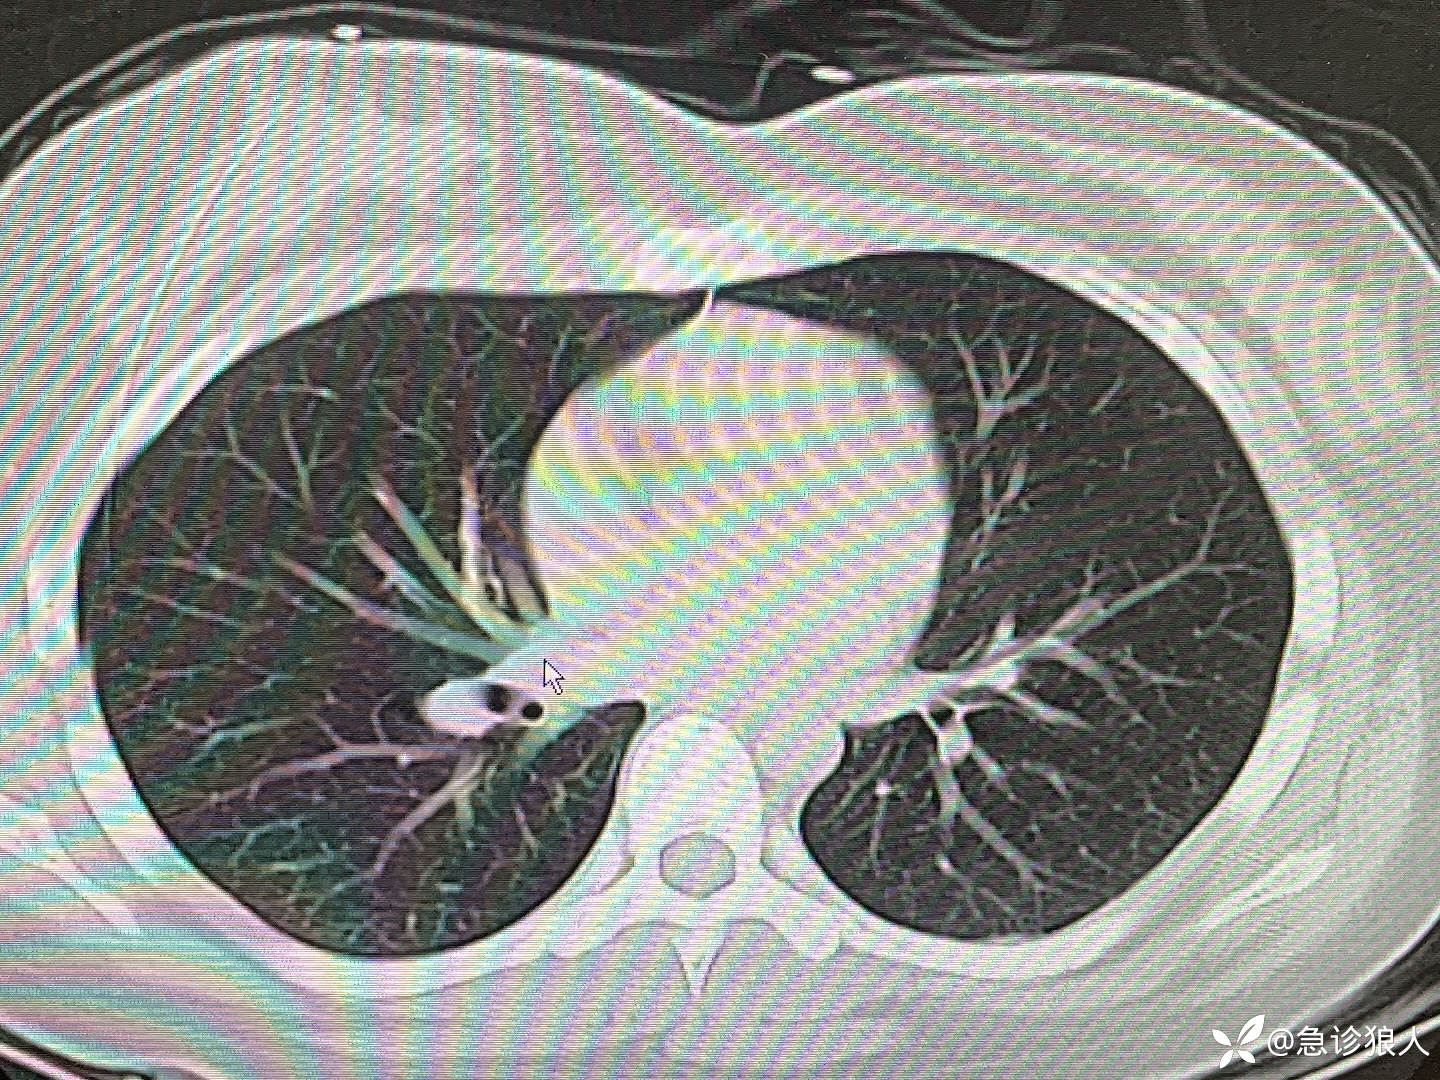

走去留观区的路上,我问,“啥病啊?”

“你们门诊很忙,我就看了个发烧的,烧退了,他就感觉很难受,一直抱着被子,抖。”

快速走到病人床旁,患者,男,44岁,生命体征平稳,我问,“怎么不舒服?”

病人抱着被子,手颤抖着,说,“就是很难受。”

“冷吗?”

“也不冷?”

“原来什么病?”

“一个月前刚切了甲状腺。”

快速走到电脑旁,患者的实验室检查如下:

看完检查,我笑着看向急诊外科医生,“我想说不知道他咋了的,但我确实知道他怎么了!”

“你快说他咋了。”

(你们猜患者怎么了?)

“你看他这个血钙1.87,白蛋白正常,这个钙已经很低了,甲状腺手术后1个月,很明显甲状旁腺受损了吧!现在的症状就是缺钙的症状,发烧应该是诱因,现在你给补上钙,应该症状就能好转。”

“咋补?”

“你这葡萄糖酸钙3支➕10%葡萄糖20ml,60ml/h,快速给他泵进去就行了,别忘了查个甲状旁腺激素。”